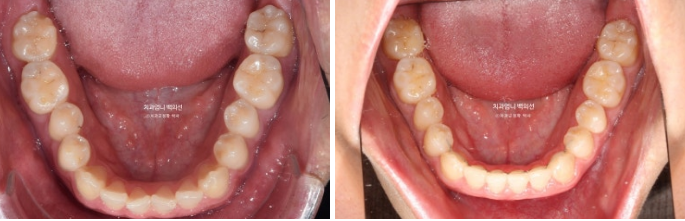

23.01~25.03

The upper arch widened through the palatal expansion device